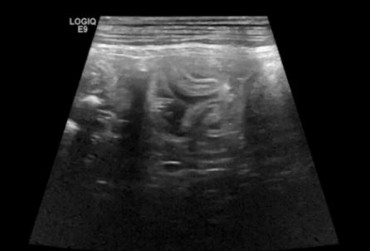

Pies, owczarek szetlandzki 6l. Mukocele. - 2

24 czerwca 2019

Wojciech Atamaniuk

Pies, owczarek szetlandzki 6l. Mukocele. - 1